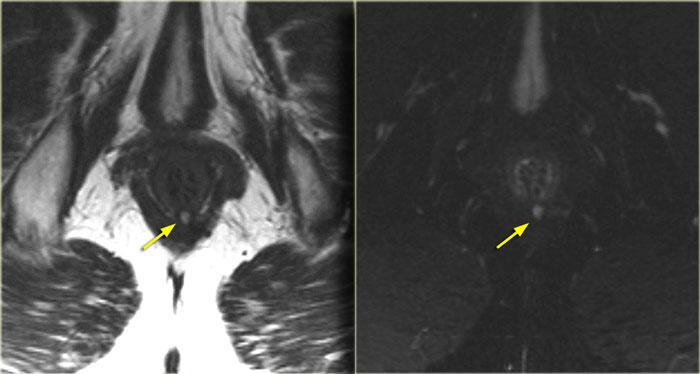

Bên trái là hình ảnh cắt ngang chuỗi xung T2W có và không có xóa mỡ.

Một đường rò liên cơ thắt nằm ở vị trí 6 giờ.

Tiếp tục xem hình ảnh mặt phẳng coronal.

Trên hình ảnh coronal, đường rò chạy xuống phía dưới về phía da.

Không có sự kết nối với cơ thắt ngoài.